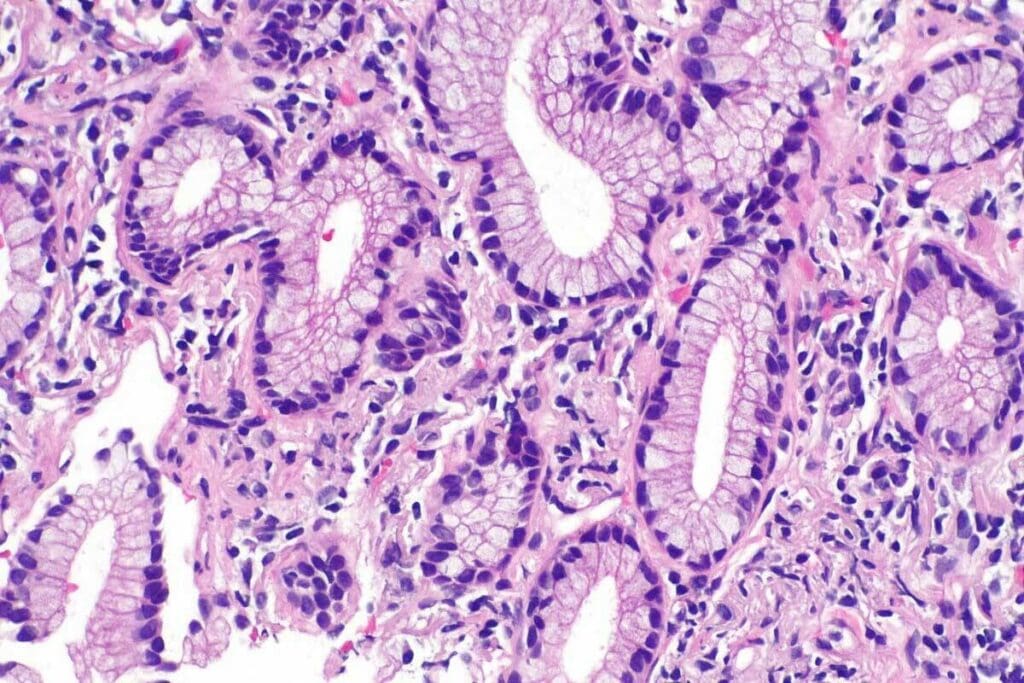

What is Adenocarcinoma and Where Does It Occur?

Adenocarcinoma starts in gland cells. It can happen in places like the breast, colon, lung, and prostate. Studies show it’s the most common cancer in some groups. Where it occurs affects how it’s treated.

Because it starts in gland cells, adenocarcinoma can show up differently. For example, lung adenocarcinoma is not the same as breast adenocarcinoma. This means each type needs its own treatment plan.